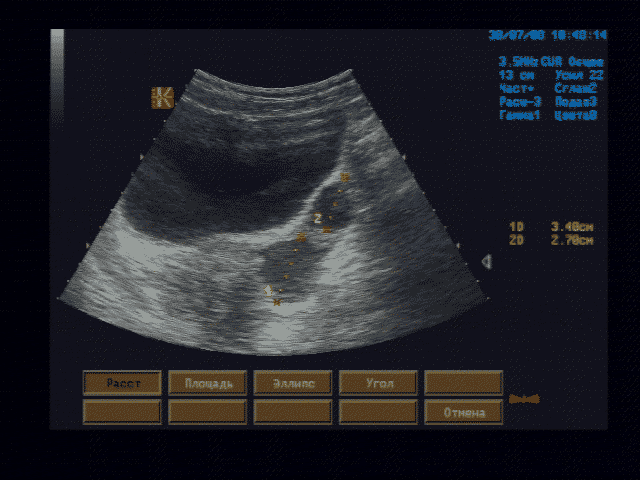

Контрон СИГМА 210, ирис. Электронные линейный датчик 7,5 МГц и конвексный - 3,5 МГц

Печень - границы печени не расширены: нижний край правой доли у рёберной дуги, незначительно закруглён, переднезадний размер правой доли 119 мм, косой вертикальный 148 мм, переднезадний размер левой доли 59 мм, вертикальный 93 мм; контуры ровные, диафрагмальный контур нечёткий, паренхима неоднородная за счет гипоэхогенного участка вблизи правой боковой стенки желчного пузыря, имеющего округлую форму, диаметром 15 мм, имеющего ровные, относительно четкие контуры, однородное внутреннее строение; на остальном протяжении паренхима однородная, эхоструктура диффузно повышенной эхогенности рисунок зернистости нечёткий; внутрипечёночные жёлчные протоки не расширены, свободны, сосудистый рисунок обеднен.

Эхографические признаки хронического гепатита, гипоэхогенного очага 5 сегмента печени.